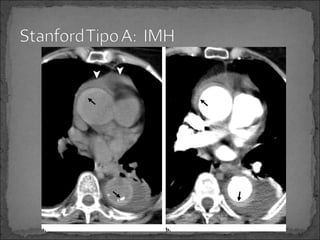

Stanford tipo A:

 75 por ciento

 Reparación inmediata para evitar complicaciones fatales

Extensión hacia el pericardio, espacio pleural, arterias

coronarias o al anillo aórtico valvular.

Es comúnmente clasificado con Stanford

IMH Stanford tipo A. Tratamiento Quirúrgico